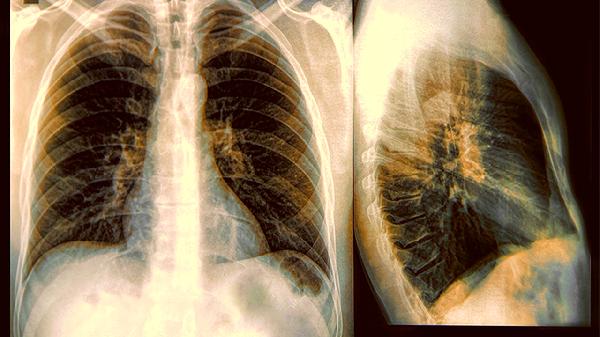

肺癌早期筛查不能只依赖胸部X光片。建议40岁以上高危人群每年做一次低剂量螺旋CT检查,其检出率是胸片的4-10倍。若发现双腿出现上述异常信号,不妨及时就诊排查。健康生活方式与定期体检双管齐下,才能更好地守护呼吸健康。